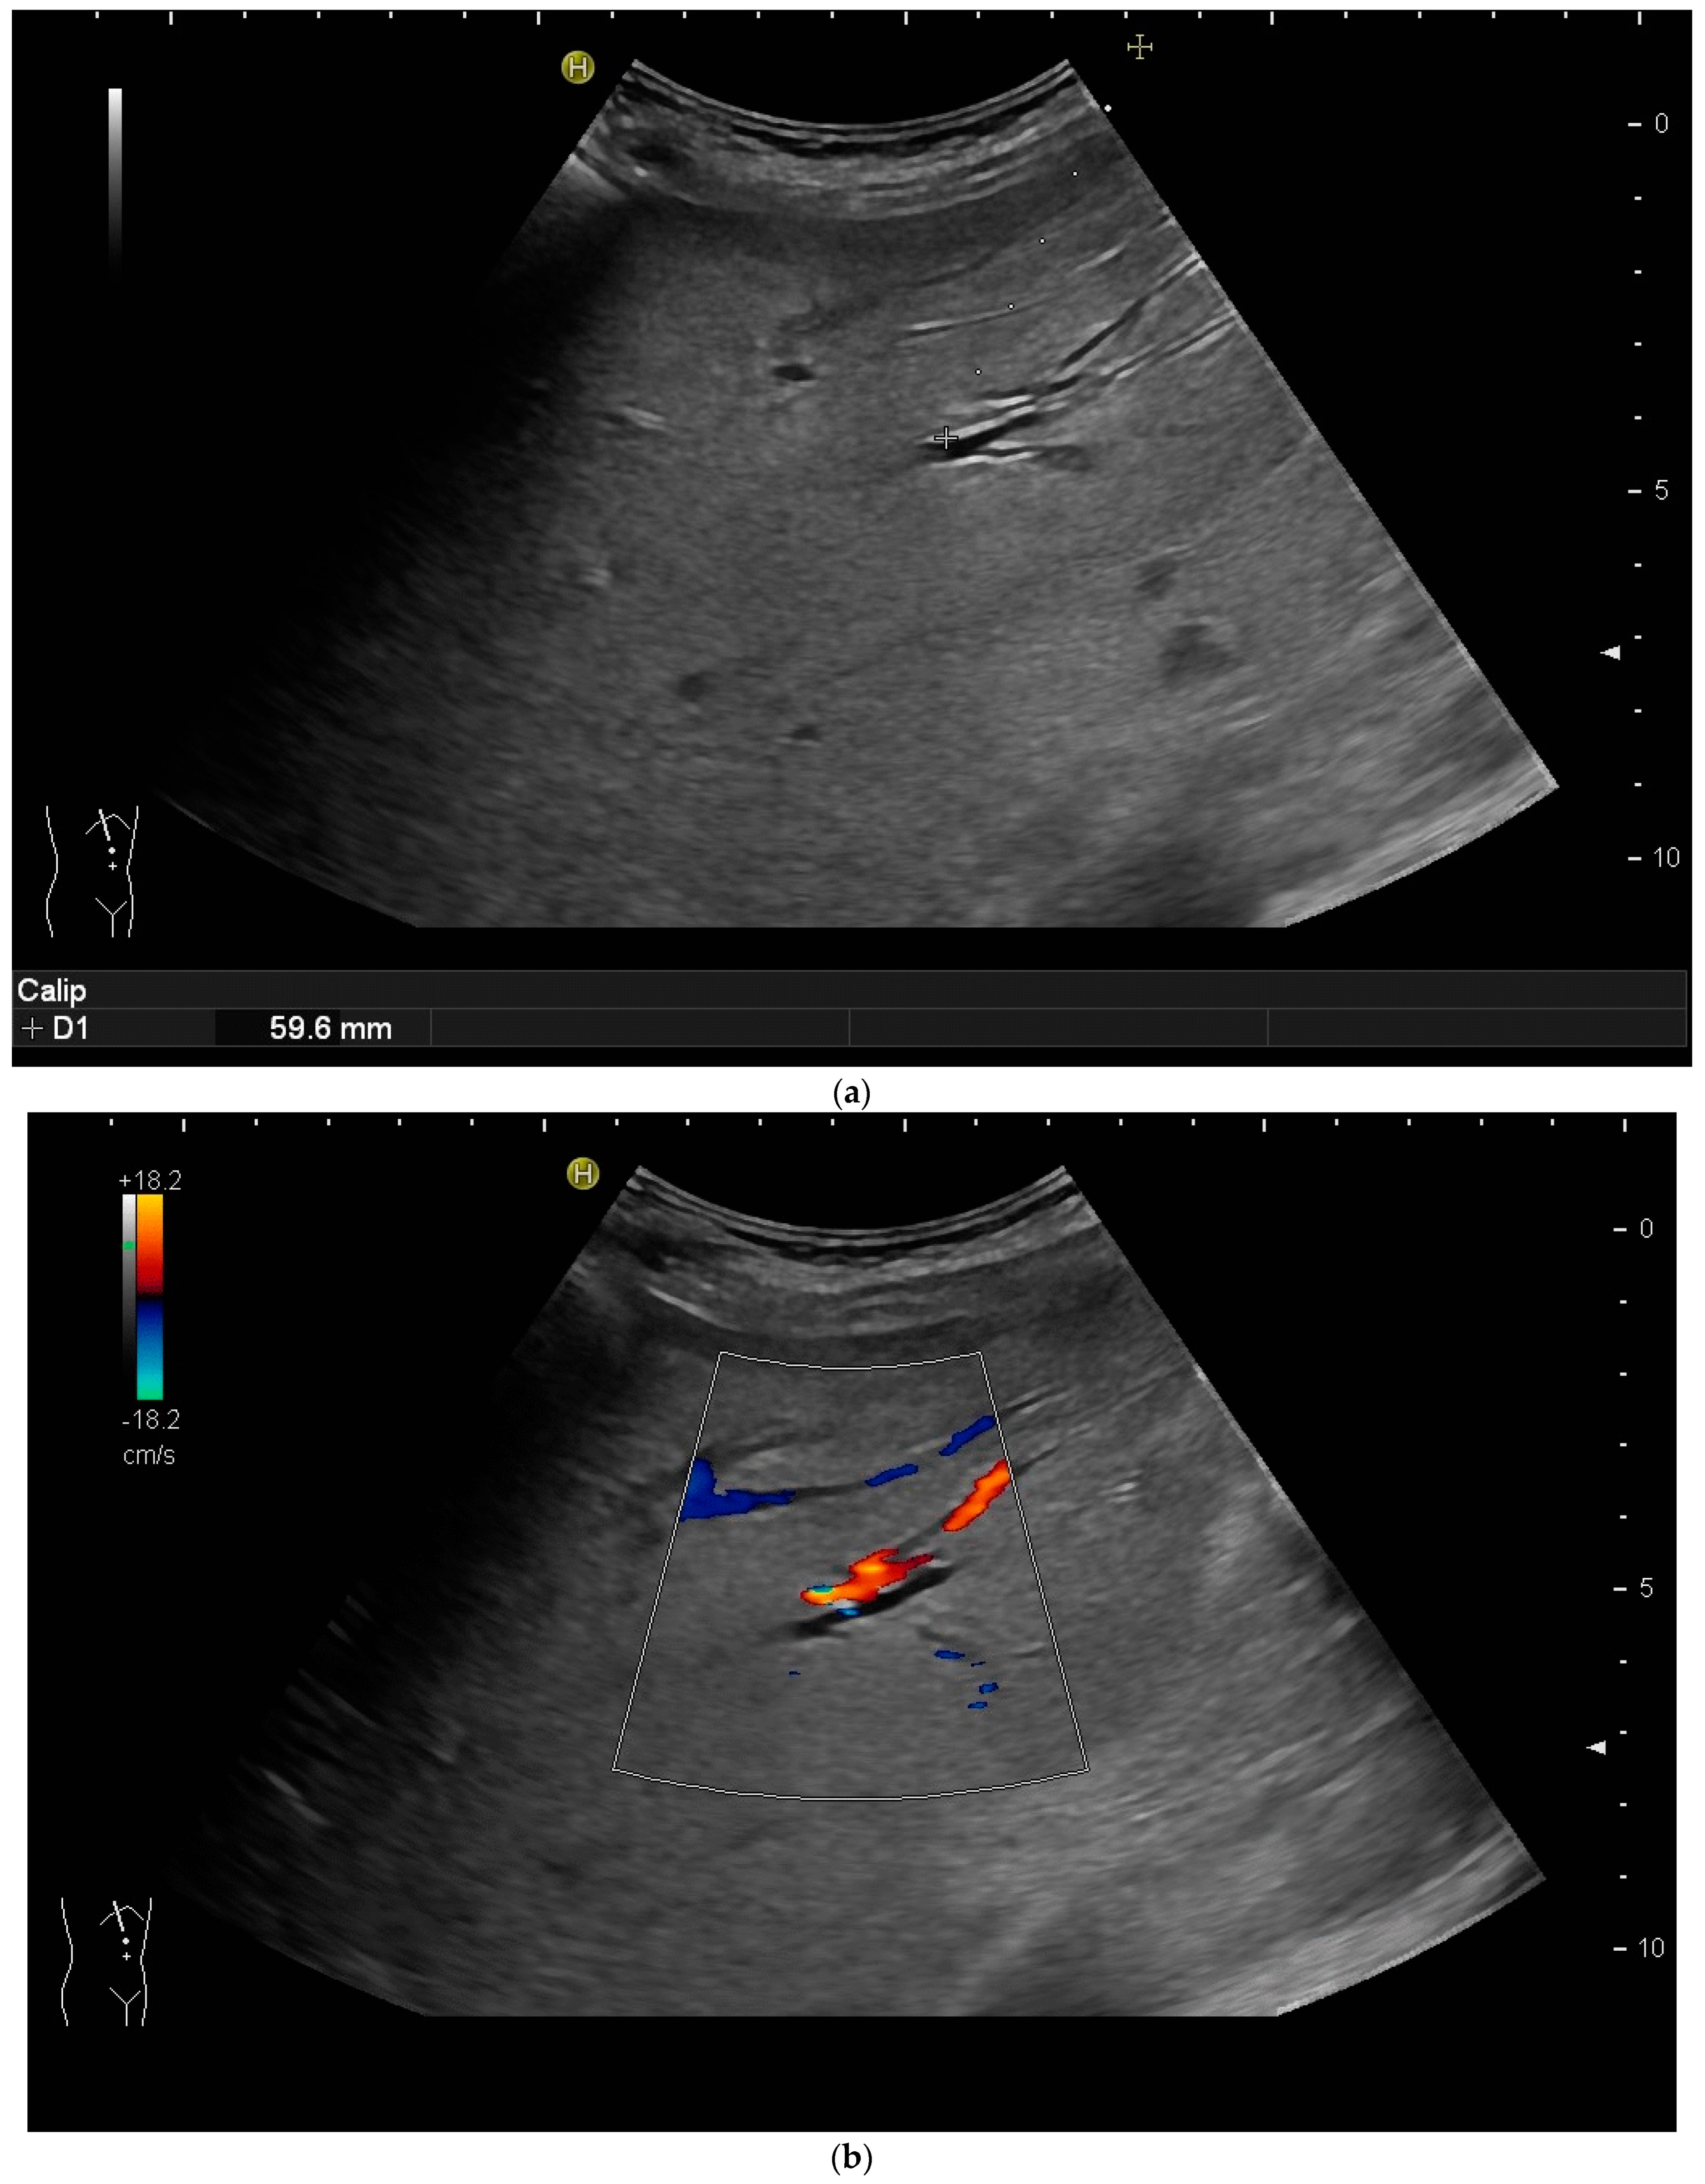

The biliary system can be punctured in the right or left liver lobe, depending on the level of obstruction or medical needs. In dilated intrahepatic ducts, accessing the bile ducts with a needle and advancing a wire with the subsequent placement of drainage is easier, and adverse events are fewer than in nondilated ducts. It is also possible to access nondilated ducts, but ideally, a duct with a diameter of ≥3 mm should be aimed for. As bile ducts run in parallel to portal veins, nondilated bile ducts can be found by using colour Doppler and heading for a portal vessel visualised thereby—the so-called parallel technique [20,31,37,38,39]. Ideally, the angle between the duct and needle should be less than 90 degrees [40].

However, the “free hand” technique allows for every puncture angle and is, therefore, preferred by us. The use of colour Doppler will enable the doctor to avoid blood vessels and identify smaller bile ducts (Figure 3a,b).

Figure 3.

(a) Hypoechoic tubular structures in Segment V are visualised in an intercostal view; (b) Colour Doppler helps to differentiate between bile ducts and blood vessels.